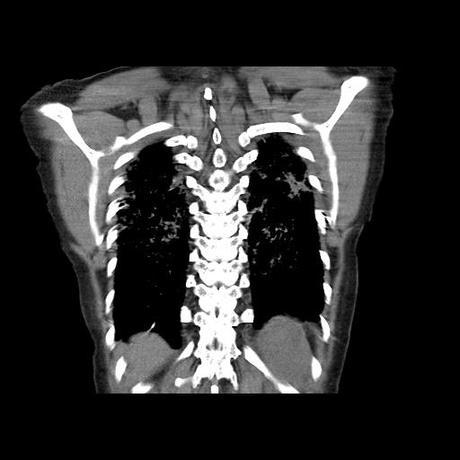

Se realiza volumen de tórax en fase simple, desde los opérculos torácicos hasta los hemidiafragmas, observándose:

El parénquima pulmonar con areas parcheadas difusas en vidrio despulido combinadas con otras areas hipodensas de baja atenuación debidas a atrapamiento aéreo y engrosamiento intersticial y zonas de fibrosis de predominio en lóbulos medios e inferiores de ambos pulmones.

- LOS HALLAZGOS PUEDEN ESTAR EN RELACIÓN A NEUMOPATIA INTERSTICIAL PROBABLE ETIOLOGIA HIPERSENSITIVA VS AUTOINMUNE/BACTERIANA/FUNGICA.